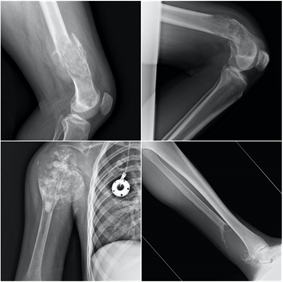

Quiste óseo aneurismático

El quiste óseo aneurismático, aunque es un tumor benigno, es localmente agresivo. Constituye alrededor del 2% de los tumores benignos del hueso en menores de 20 años. En las radiografías se suele observar una lesión lítica y expansiva con elevación del periostio y en ocasiones márgenes mal definidos que recuerdan a una lesión maligna, por lo que podría precisar biopsia y análisis anatomopatológico en algunos casos. La fractura patológica se produce hasta en el 30% de los casos, precisando estabilización quirúrgica en caso de fracturas desplazadas y tratamiento específico con aporte de injerto óseo para su tratamiento definitivo.

Osteocondroma

El osteocondroma es la neoplasia más frecuentemente observada en el esqueleto. El osteocondroma es un tumor benigno que contiene hueso y cartílago. Forma unas excrecencias óseas recubiertas por cartílago en torno a las metáfisis de los huesos largos. Es muy frecuente en las zonas cercanas a la rodilla. También puede aparecer en el hombro y en los huesos del antebrazo. Es frecuente detectarlos en la adolescencia, pues la lesión puede provocar fenómenos inflamatorios con el roce sobre los tejidos blandos periarticulares, músculos o tendones. En caso de dolor y limitación se puede realizar cirugía, habitualmente con buenos resultados.